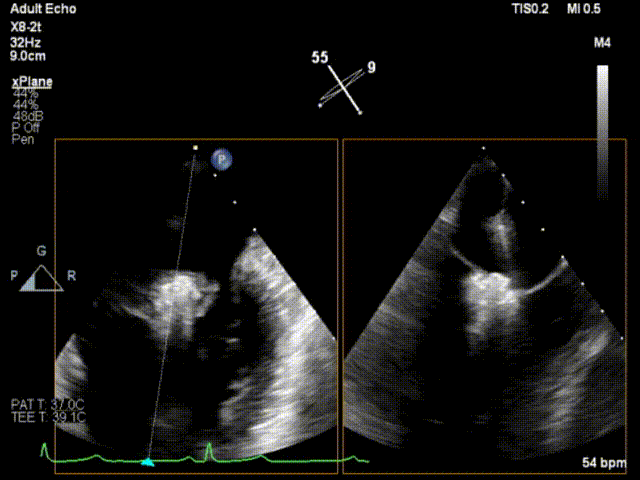

手术运用DSA与三维经食道超声心动图监测,通过患者股静脉穿刺房间隔途径建立夹合器输送轨道,将夹合器送进左心房,借助夹合器输送系统通过病变的二尖瓣部位,在心脏不停跳的状态下快速完成二尖瓣脱垂瓣叶的破获和夹合,夹合位置满意,超声提示反流降至1+,遂释放夹合器,反流最终程度为1+,结束手术,手术过程耗时一小时左右。

释放夹子

术后即刻超声心动图